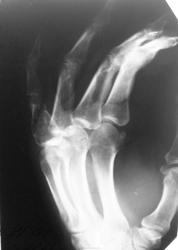

Пол пациента: Женский пол Тип патологии: Травма Область исследования: Скелетно-мышечная система Методы исследования: Rg Мужчина 38 лет, с травмой кисти направлен для исключения перелома........ пардон за качество ) https://radiomed.ru/sites/default/files/styles/case_slider_image/public/user/16833/20121211_095016.jpg?itok=cQfG31Hk ID:25089 Ср, 12/12/2012 - 14:42 #1 Катенёв Валенти... Не на сайте Был на сайте: 7 лет 3 недели назад Зарегистрирован: 22.03.2008 - 22:15 Публикации: 54876 Снимок конечно не фонтан, но предположить можно энхондрому. Ср, 12/12/2012 - 14:46 #2 Mihail63 Не на сайте Был на сайте: 9 лет 9 часов назад Зарегистрирован: 20.11.2012 - 10:31 Публикации: 154 Перелома не вижу +1 за энхондрому проксимальной фаланги 5 пальца Ср, 12/12/2012 - 19:44 #3 И.Бондаренко Не на сайте Был на сайте: 18 часов 48 минут назад Зарегистрирован: 13.09.2011 - 22:55 Публикации: 9206 Патологическмий перелом основной фаланги. Ср, 12/12/2012 - 20:38 #4 Сан Саныч1 Не на сайте Был на сайте: 11 месяцев 3 недели назад Зарегистрирован: 07.06.2010 - 21:17 Публикации: 2114 А что насчет болезни имени простого русского мужика Реклингхаузена? Хочешь сделать что-то нормально - сделай это сам! Ср, 12/12/2012 - 20:58 #5 Наталия Васильевна Не на сайте Был на сайте: 5 лет 9 месяцев назад Зарегистрирован: 25.09.2011 - 09:02 Публикации: 754 Или гигантоклеточная с переломом основания. Ср, 12/12/2012 - 23:03 #6 Special.K Не на сайте Был на сайте: 8 лет 10 месяцев назад Зарегистрирован: 09.08.2012 - 23:08 Публикации: 479 Наталия Васильевна wrote: Или гигантоклеточная с переломом основания. я в заключении написал именно так. перелом проксимального эпифиза основной фаланги и подозрение на новообразование (дифф. диагноз с ГКО). Ср, 12/12/2012 - 23:10 #7 vasyablack Не на сайте Был на сайте: 12 лет 3 недели назад Зарегистрирован: 22.03.2012 - 23:38 Публикации: 53 1.энхондрома 2.киста Чт, 13/12/2012 - 19:15 #8 НБ Не на сайте Был на сайте: 11 лет 5 месяцев назад Зарегистрирован: 07.11.2012 - 19:55 Публикации: 84 Костная киста, патологический перелом. Н.Б. Пт, 14/12/2012 - 17:17 #9 Брысковский Дмитрий Не на сайте Был на сайте: 9 месяцев 2 недели назад Зарегистрирован: 08.11.2011 - 11:00 Публикации: 187 пункция в помощь исследователю) None are more hopelessly enslaved than those who falsely believe they are free

Снимок конечно не фонтан, но предположить можно энхондрому.

Перелома не вижу

+1 за энхондрому проксимальной фаланги 5 пальца

Патологическмий перелом основной фаланги.

Или гигантоклеточная с переломом основания.

я в заключении написал именно так. перелом проксимального эпифиза основной фаланги и подозрение на новообразование (дифф. диагноз с ГКО).

1.энхондрома

2.киста

Костная киста, патологический перелом.